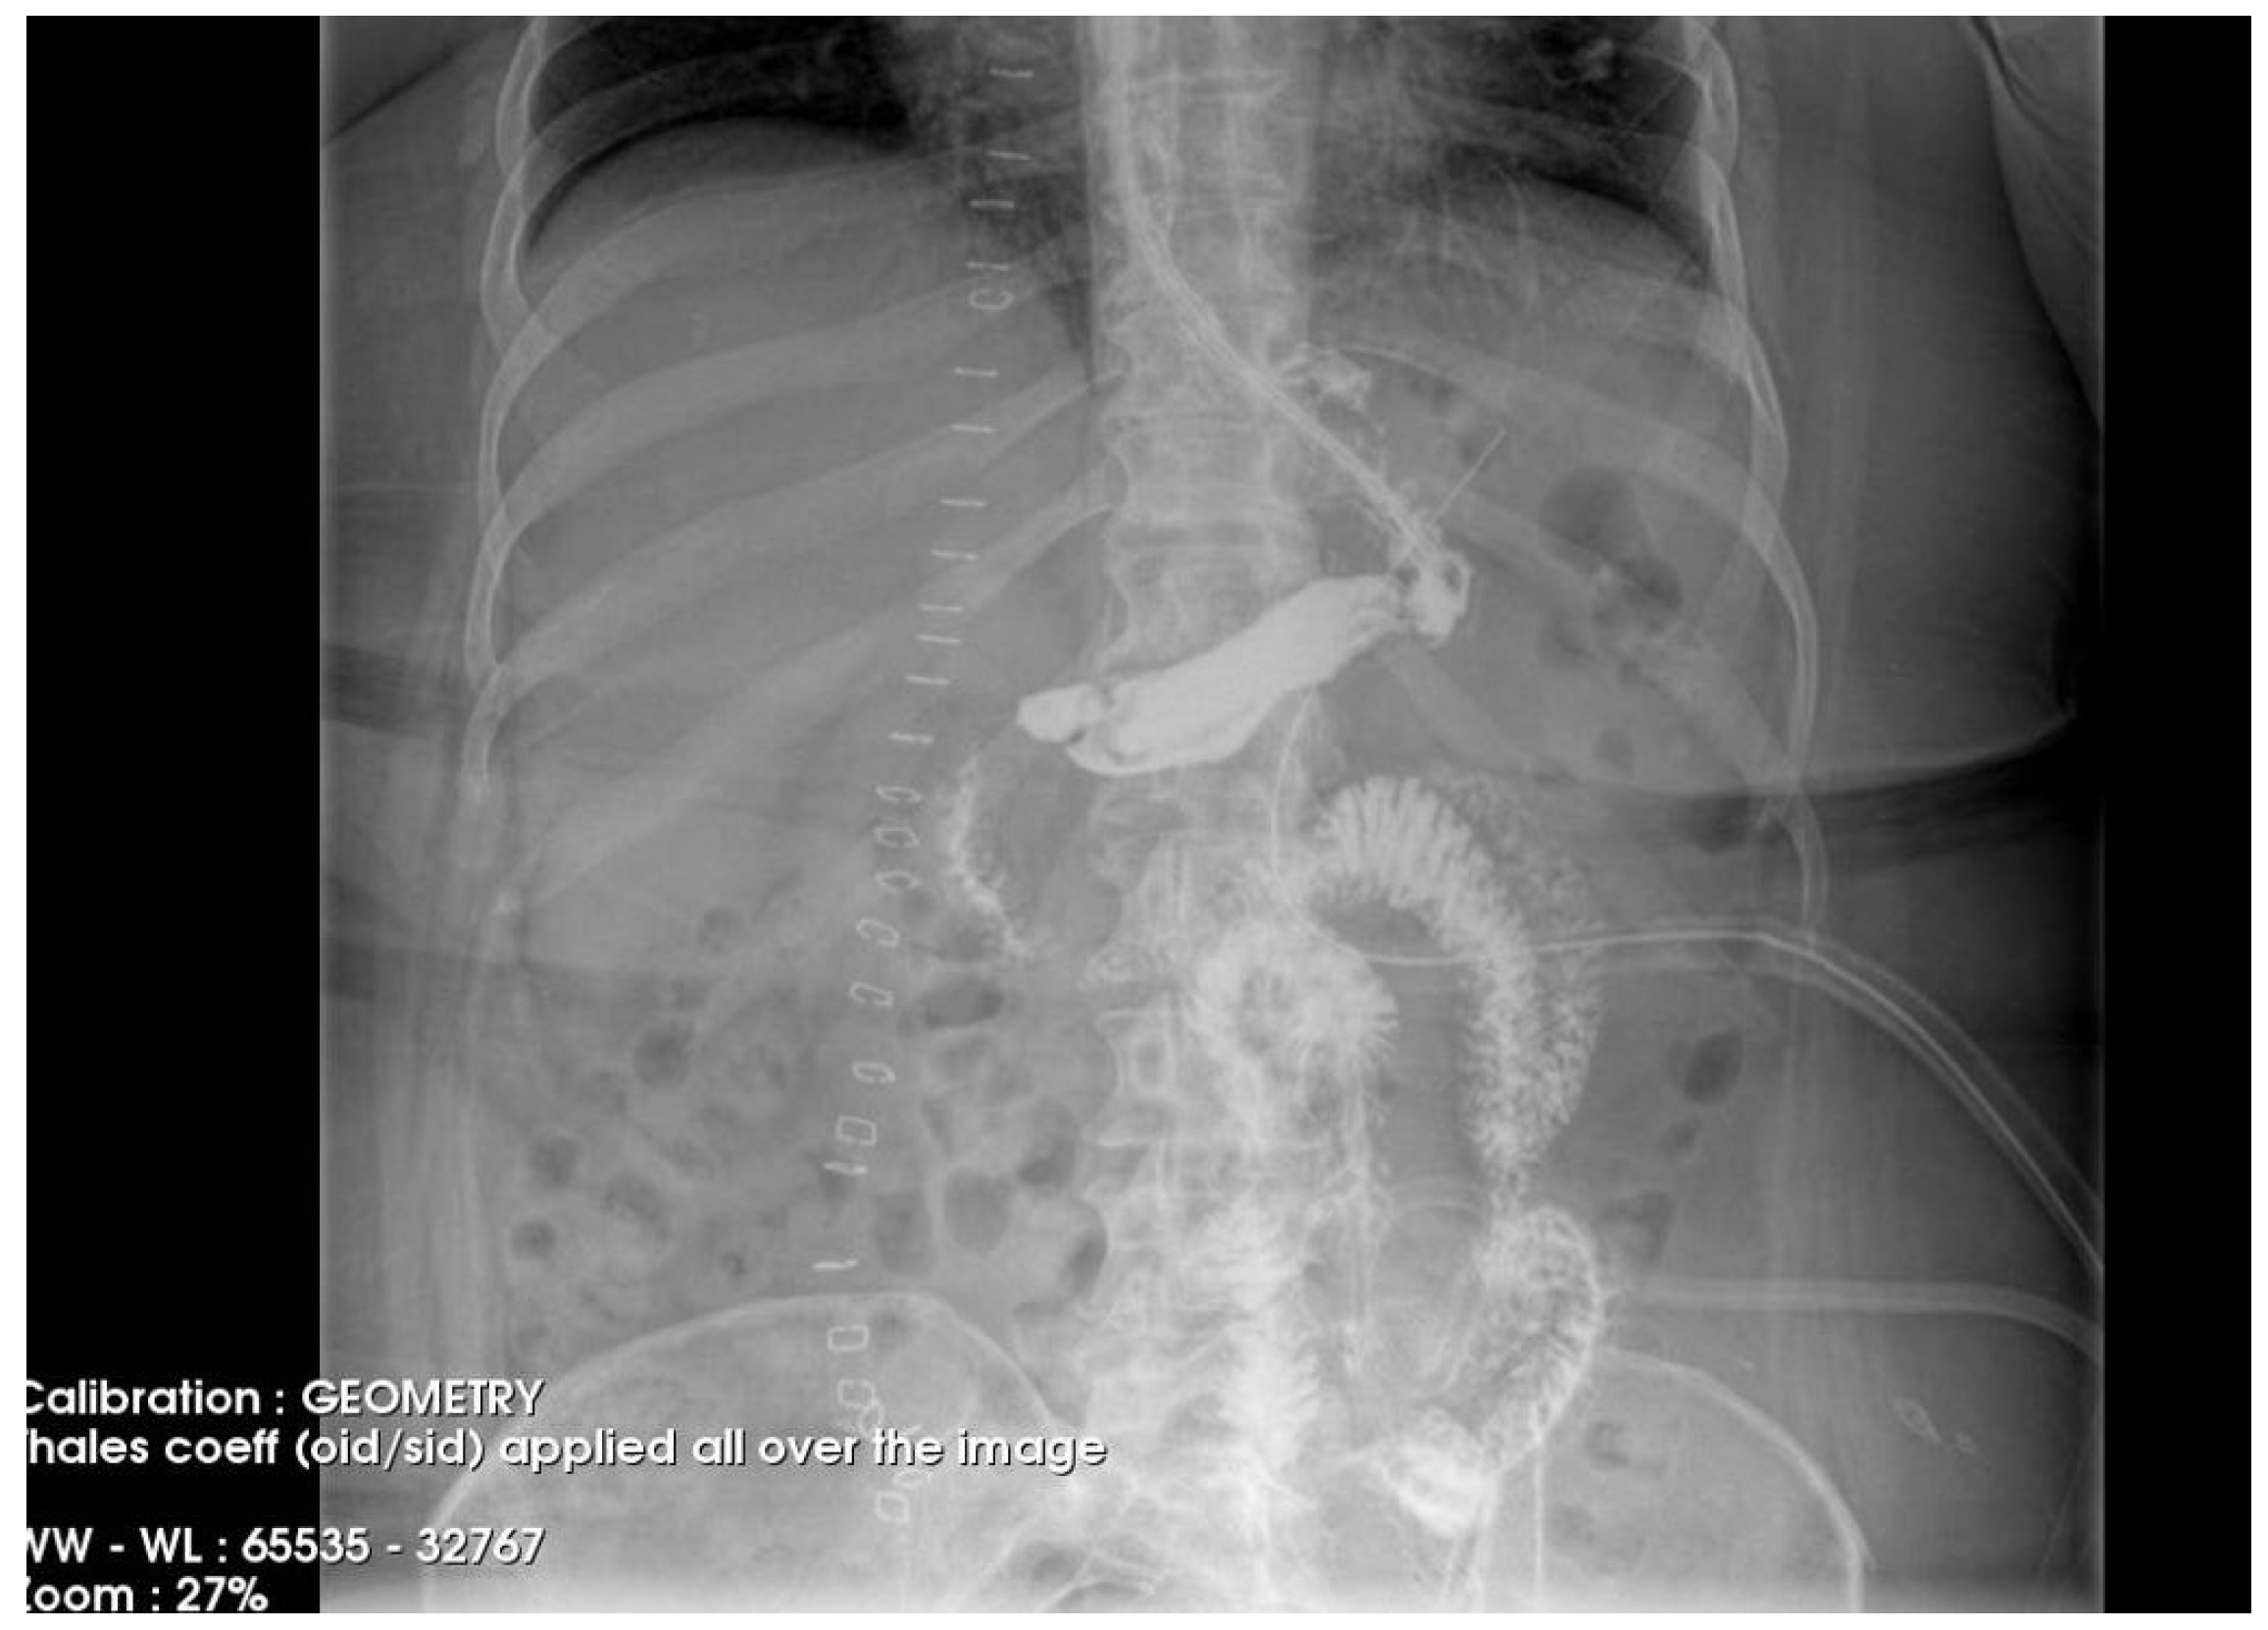

To gain a more comprehensive understanding of the patient’s condition, a contrast-enhanced abdominopelvic computer tomography (CT) scan was performed. Imaging revealed a reduced gastric volume with the nasogastric tube in place, previously positioned with its distal tip at the subcardial region (Figure 1a,b). In the gastric fornix, two parietal defects were observed, measuring 13 mm (on the posterior wall) and 3 mm (on the anterior wall), with the passage of orally administered contrast substance into the fat of the gastro-splenic ligament. Near the greater curvature of the stomach, a few gas bubbles were present in the omental fat. Further investigations were carried out, including an endoscopic examination, which revealed the esophagus with a 20 mm lumen and tertiary contractions. Additionally, a highly intense pneumatosis was observed throughout the entire colonic frame. The contrast agent administered during the procedure was later detected at the level of the left colon, further guiding the diagnostic process. Following this thorough clinical and paraclinical evaluation, the diagnosis of a high gastric fistula secondary to a gastric sleeve procedure was confirmed.

Figure 1. (a,b) Abdominal computer tomography (coronal and axial view)—parietal defects are observed with the presence of the contrast substance in abdominal cavity.